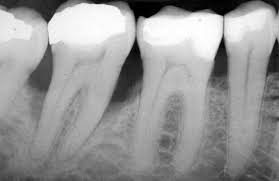

Blog from www.wrigleyvilledental.com

Those who don't have cavities can go a year or two between.